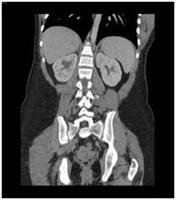

Before even hearing those words my consultant was pre empting. As soon as he found something suspicious he got my bloods tested and a CT Scan done, on the same day. Bearing in mind I was slightly off my face on concious sedation the day was a bit of a blur, which in hindsight isn’t a bad thing.

Another appointment with Mr B (consultant) we were told that my CT did not show any large masses, but we still needed histology. The bad news at this stage was being told that the next steps were the panproctocolectomy, total hysterectomy and bilateral salpingo oophorectomy. Try saying that after a few large vinos!

What I needed was my TNM, which is what tells you the stage of cancer by looking at its size, where it is and if there is any spread. To do this I had to wait til after surgery for full histology on all my organs.

Long winded post to get to this point but these images below, from Bowel Cancer UK, help explain it.